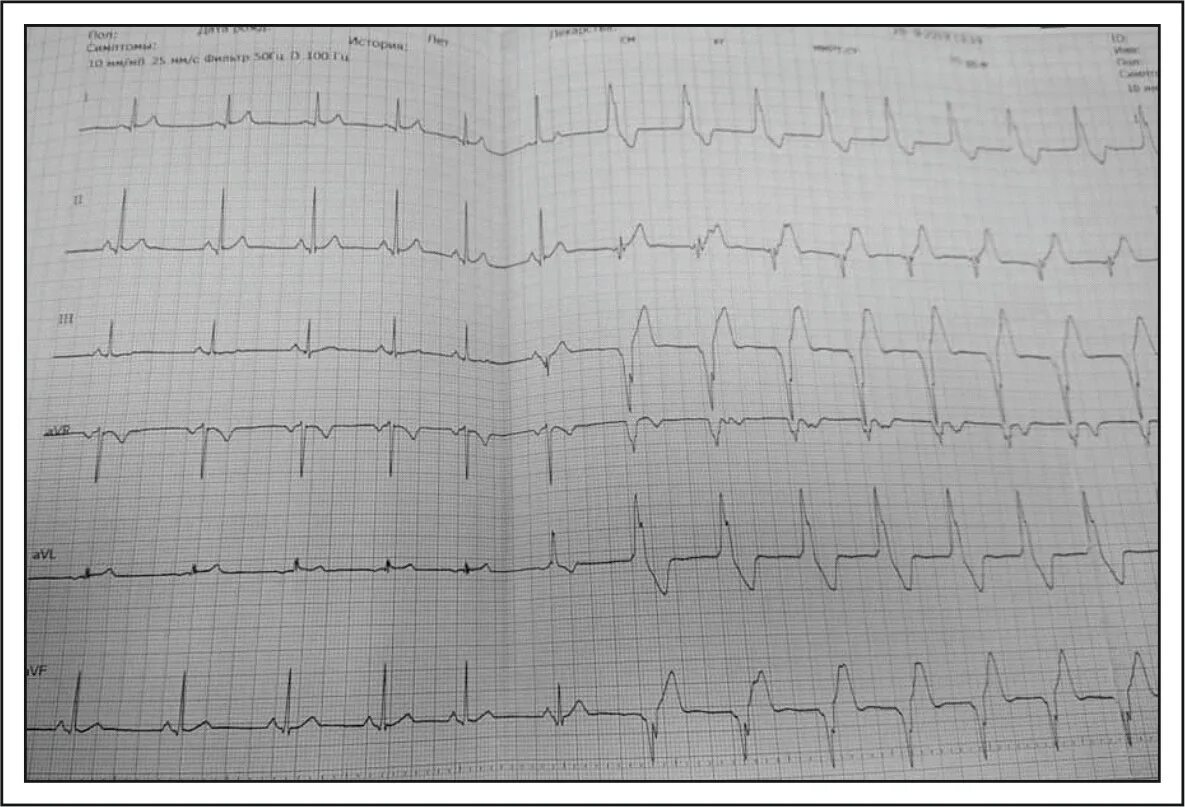

Широкий комплекс qrs